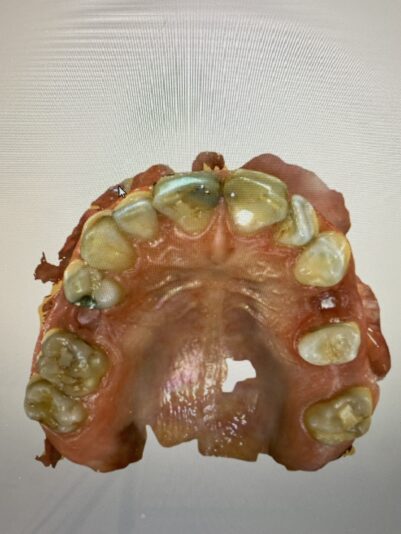

Here are his scans. Not sure if this bite is entirely accurate but there is no contact on the two centrals.

-